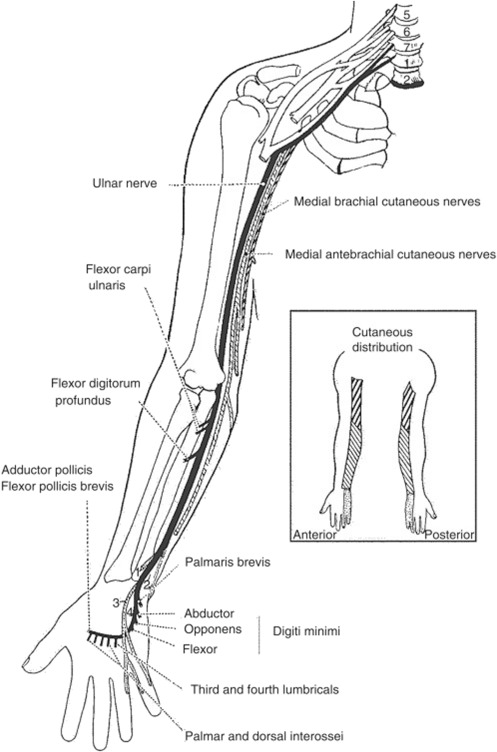

Nervio ulnar: trayecto en el brazo

¿Qué hace el nervio ulnar en el brazo?

Origen: fascículo medial (C8-T1)

Trayecto: surco bicipital medial → perfora tabique intermuscular medial en tercio distal → pasa a compartimento posterior

Pasa por detrás del epicóndilo medial (surco del nervio ulnar) → muy superficial → vulnerable a golpes ("hueso de la risa")

No da ramos musculares en el brazo → solo pasa

Nervio ulnar en el antebrazo

¿Qué inerva el nervio ulnar en el antebrazo?

Llega desde atrás del epicóndilo medial → entra al antebrazo entre las dos cabezas del flexor ulnar del carpo

Solo inerva 2 músculos en el antebrazo:

Flexor ulnar del carpo

Flexor profundo de los dedos (mitad medial, dedos 4-5)

Trayecto: sobre el flexor profundo, cubierto por el flexor ulnar del carpo

Se hace superficial en tercio distal → lateral al flexor ulnar del carpo → pasa por canal de Guyon en la muñeca